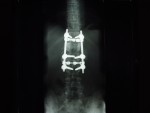

He has TWO rods in his back for support up and down... Two screws at the bottom of each rod and one at the top... He is in recovery at this time more than likely still...

He Faces a LONG three to Four months of bed rest while his back heals up... The Best of luck in all of this. The Doctors were able to do ALL of the surgery through his THIN little body Via his BACK and Did not have to cut his chest etc at all... He has 2 rods in his back and that is NOW confirmed and what I posted last night late is all good...

The hardware is coming out! On April 28th I'm gettin' this monkey off (out of) my back. Hopefully it is the source of the leg pain that has slowed the recovery process.

DSC09489.JPG

The Monkey: Side View

DSC09486.JPG

The Monkey